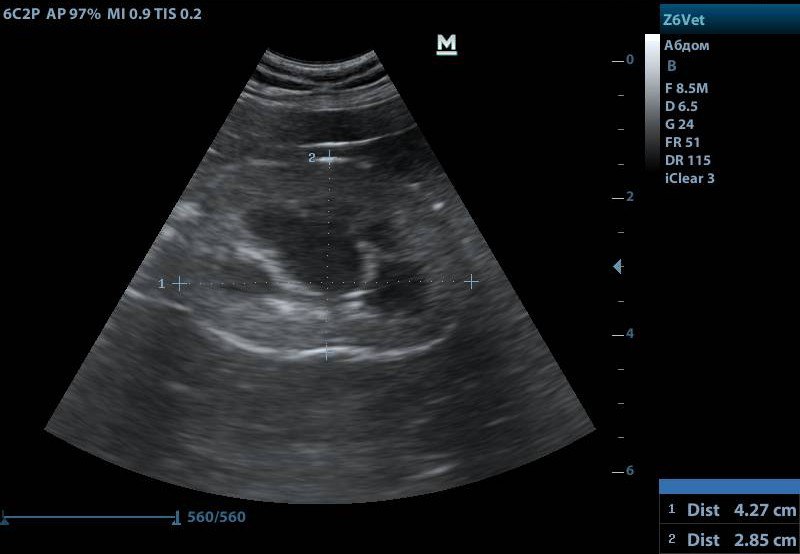

Данный диагноз ставят с помощью ультразвукового исследования. В случае поликистоза на УЗИ видно, что дифференциация слоев в почке сглажена или отсутствует. В ткани визуализируются множественные полости с жидким содержимым.

Снимок почки с поликистозом, черные включения — кисты

Если на УЗИ подтверждается поликистоз, ветеринарные врачи уже могут поставить животному диагноз «‎хроническая болезнь почек 1 стадии». В обязательном порядке исследуем кровь на биохимию, общий анализ крови и мочу на общий анализ и соотношение белок-креатинин.